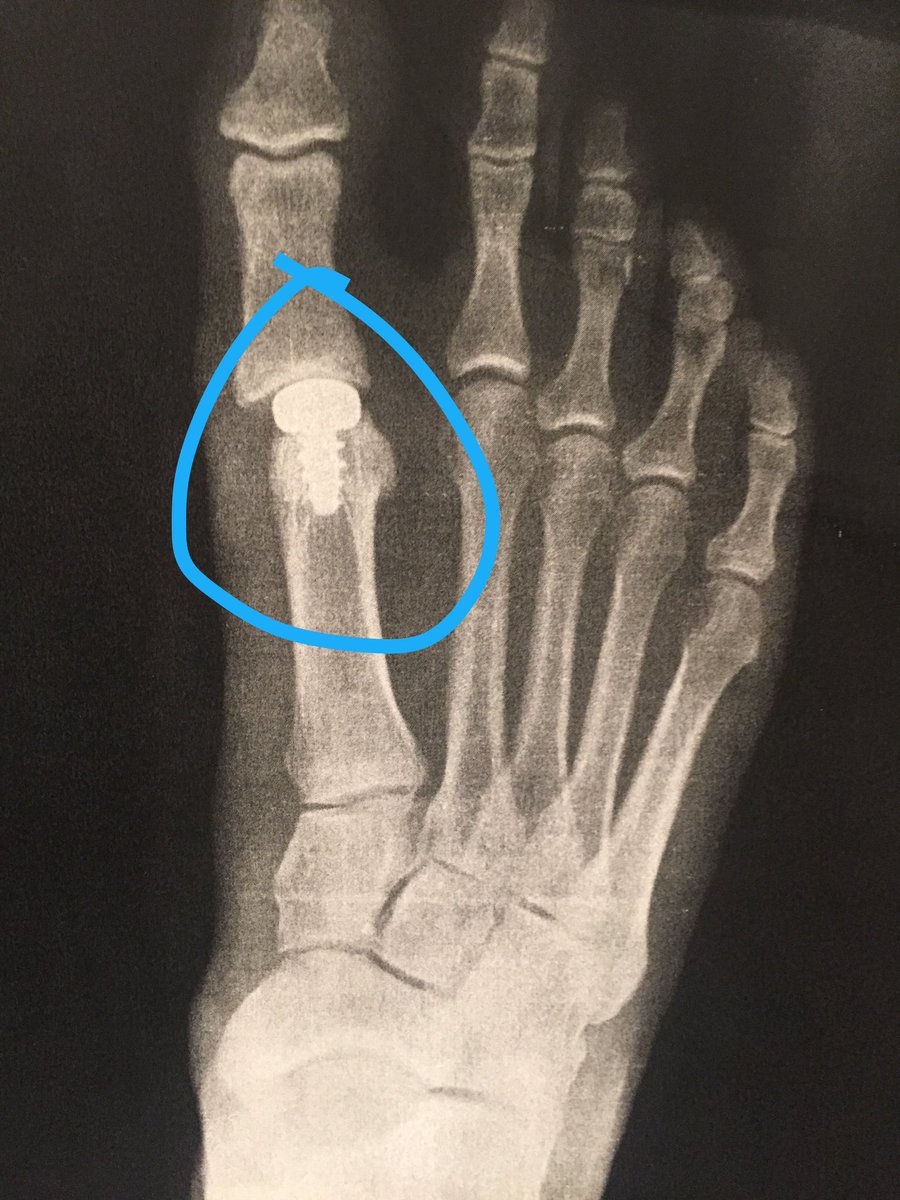

27.09.2019 · adams' specific return timeline depends on the severity of the turf toe injury. Turf toe was recognized as a common injury soon after the invention of astroturf in 1964. Pain can usually be felt immediately at the time of injury but may get worse over time as the swelling increases. One of the downsides of artificial turf may be the increase in knee, ankle, and foot joint injuries. The packers' top target in the passing game is dealing with a turf toe injury he first suffered against the philadelphia eagles on sept. Turf toe was recognized as a common injury soon after the invention of astroturf in 1964. Green bay packers receiver davante adams could miss his second straight game on monday night against the detroit lions. Turf toe injury can also develop gradually from repetitive, forced jamming through the big toe such as with quick pivoting, accelerating and jumping. 27.09.2019 · adams' specific return timeline depends on the severity of the turf toe injury. Failing to rest the mtp joint can make the injury worse. Turf toe occurs when the ligaments around the big toe joint become sprained, causing pain, stiffness, and reduced mobility. The injury usually happens when the foot sticks while the rest of the body continues forward. Turf toe injury is most commonly seen when an axial load is delivered to a foot that is fixed in equinus. Turf toe occurs when the ligament underneath the big toe hyperextends, causing a sprain. Perhaps a few days of lighter workouts or rest. Here are some other injuries that may cause foot pain similar to a. Fix it 100% satisfactorily with the right brace, splint and taping at home! A turf toe taping technique will support and protect the toe preventing it from bending in the direction that will stress the ligament causing pain. Injuries to the metatarsophalangeal region of the great toe were once considered relatively uncommon, but now are recognized as a frequent cause of morbidity and lost playing time in the athlete, particularly among american football players. The term turf toe refers to an injury of any soft tissue structure in the plantar complex, such as the plantar plate or a collateral ligament. Learn more about its symptoms, diagnosis, and treatment. A turf toe injury has 3 major grades with different recovery time and treatment. The mechanism in typical turf toe injuries is one of extreme traumatic dorsiflexion (hyperextension), often with superimposed varus or valgus angulation, which causes disruption of the plantar plate capsuloligamentous complex and allows unrestricted range of motion of the first mtp joint. It is more often seen in athletes participating in the sport of soccer especially with the increase in the use of artificial turf. Unfortunately, many times, any injury to the great toe joint that occurs during a sporting event is erroneously termed turf toe. Turf toe is a type of toe injury that most commonly affects football players, but almost any athlete can suffer from it. Grade 3 turf toe injury. Turf toe is a common sports injury that occurs when the bones and tissue around the big toe become damaged. Carbon fiber insole, rigid, shoe insert 1pc supportive orthopedic insert best for fractures, turf. With all grades there is usually some. These injuries can vary in severity — from stretching of the soft tissue to partial tearing, and even total dislocation of the mtp joint.